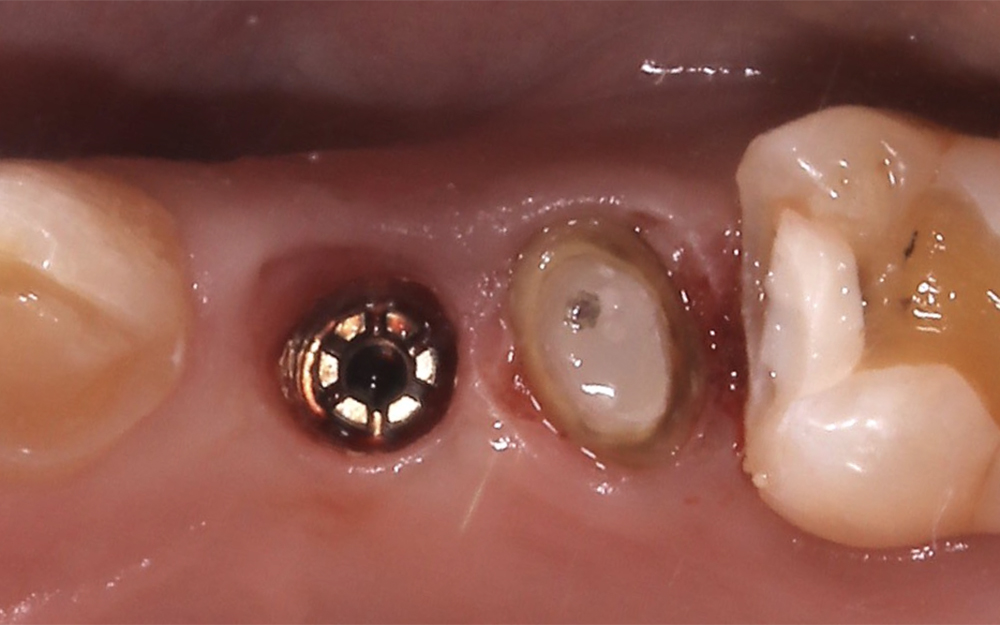

他院で抜歯してインプラントと言われ、セカンドオピニオンで来院。

ルーとメンブレンを活用したインプラント治療を行った。

虫歯の進行により左上は抜歯の診断、

ルートメンブレンテクニックを応用してインプラント治療を行った。